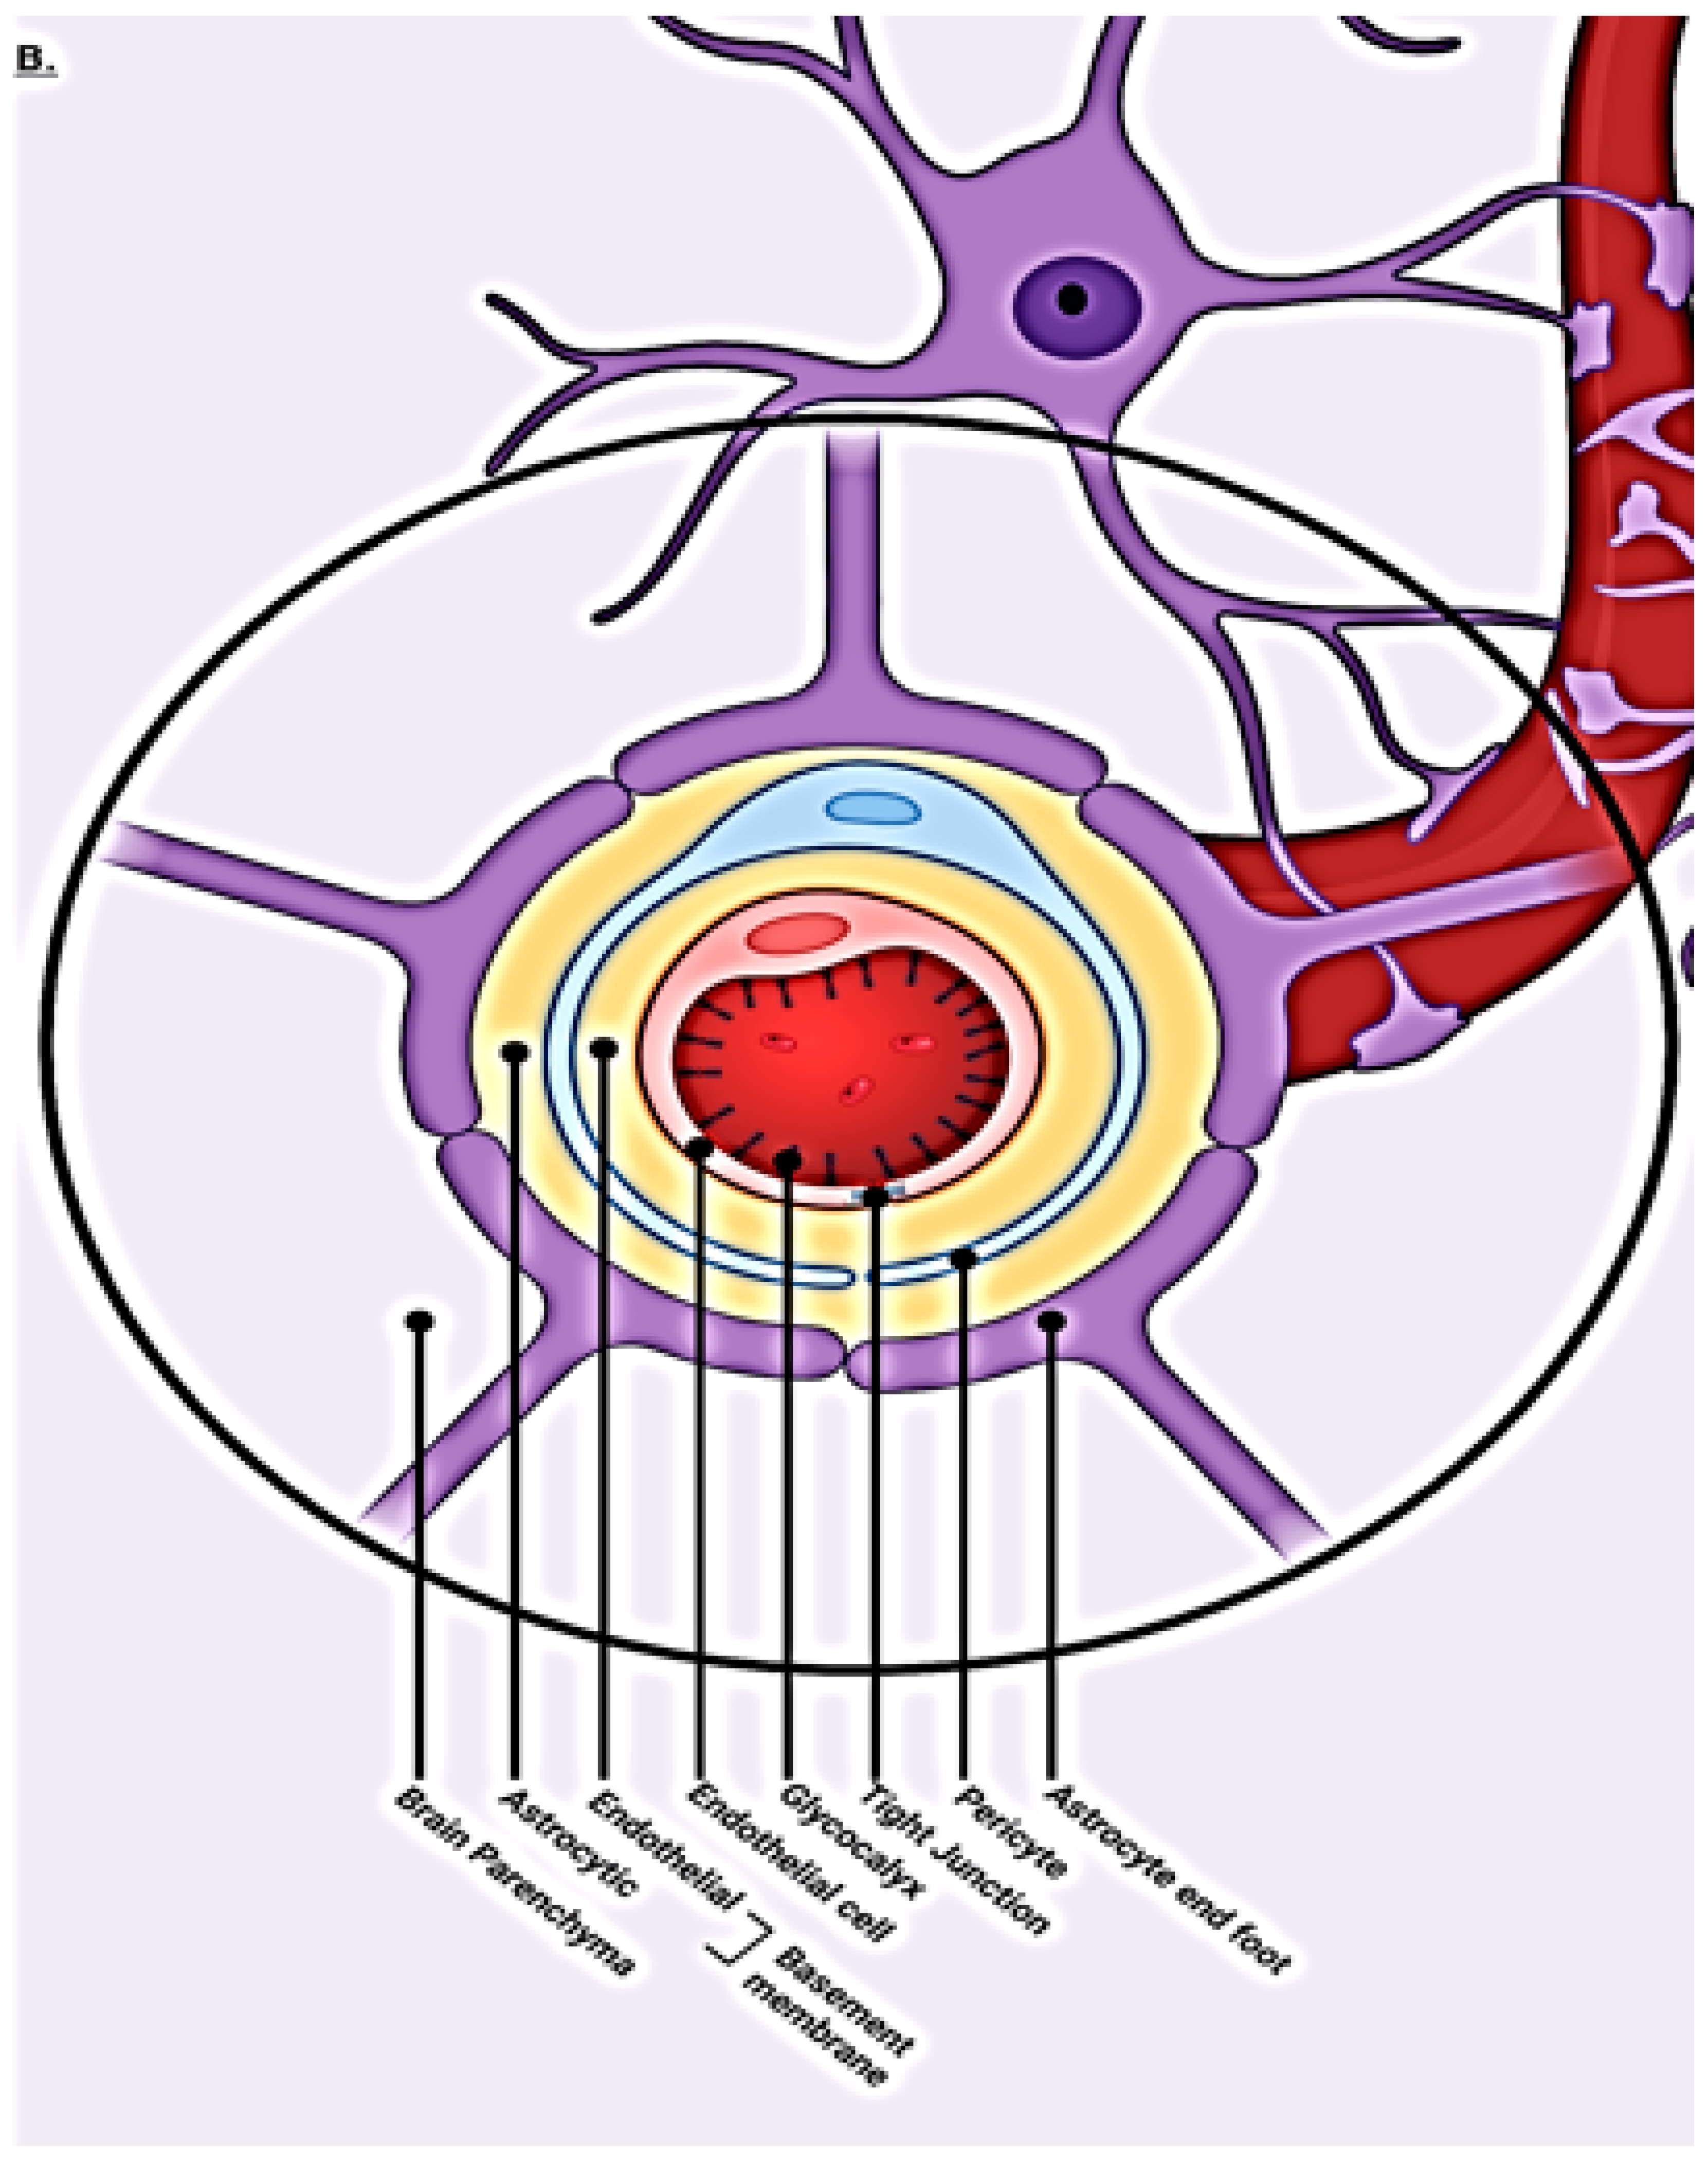

1.1. Normal BBB Physiology and Regulation

1.2. Blood–Brain Barrier Cellular Makeup and Their Function

1.3. Capillary Endothelial Cells

1.4. Pericytes

1.5. Tight Junctions

1.6. Astrocytes